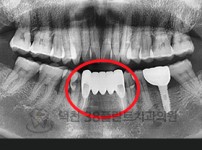

치료전후